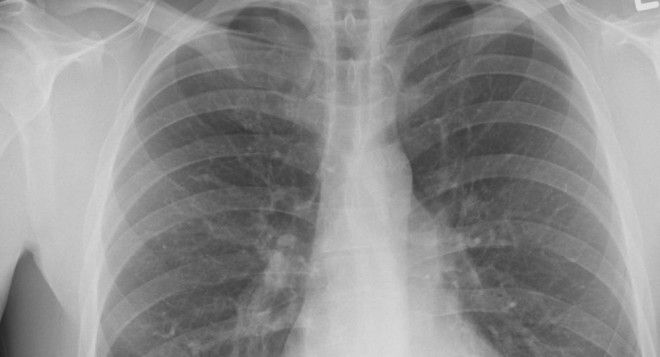

1. Что это за болезнь?

Чахотка – это устаревшее название туберкулеза. Но врачи того времени считали, что туберкулез, бронхит, грипп и воспаление легких – по сути одна и та же болезнь.

Из-за этого её часто обнаруживали тогда, когда человека уже вылечить нельзя. Многие жили в страхе, что любая простуда может закончиться для них деревянным ящиком.